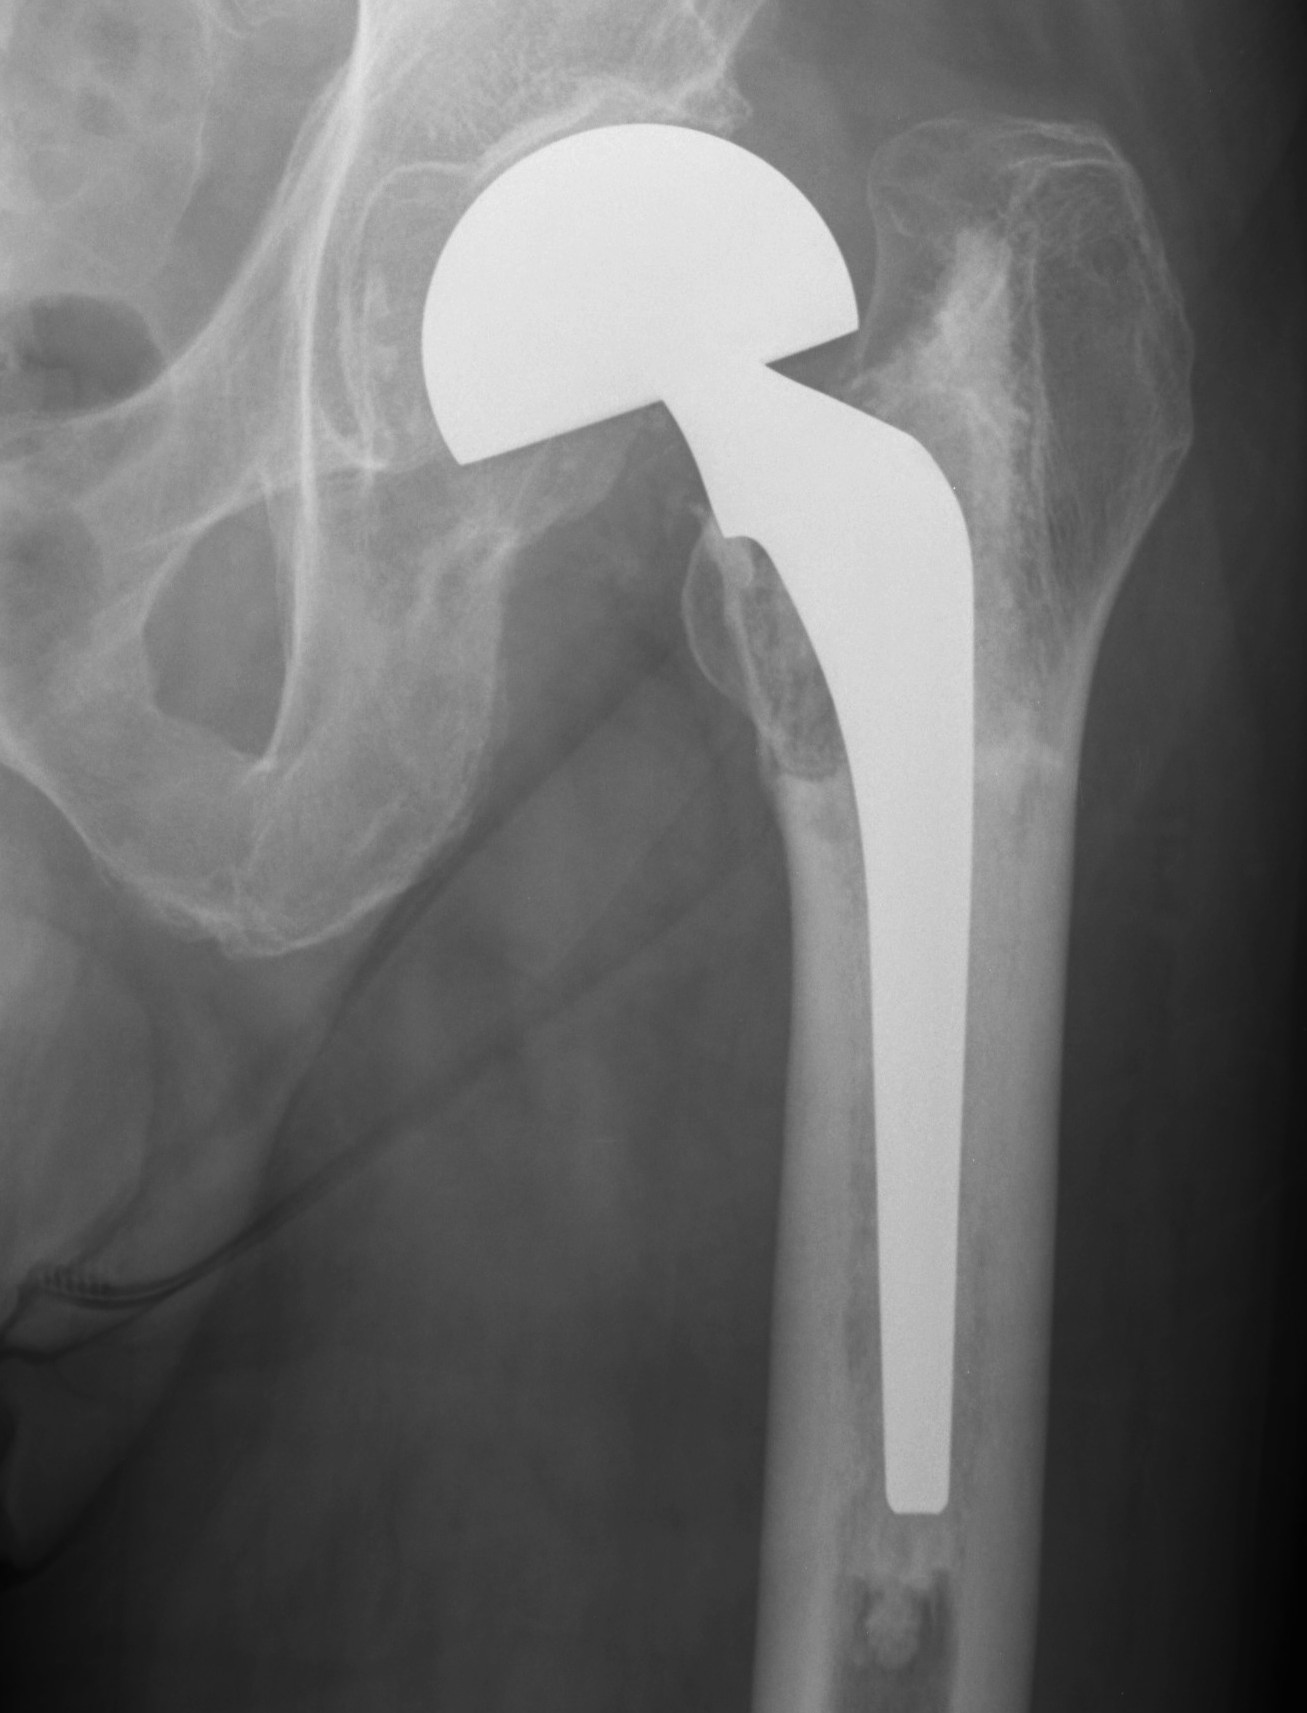

Paprosky Type 1

Definition

Minimal metaphyseal cancellous bone loss

Intact diaphysis

Options

Simple revision

- can use standard or any revision stems

A. Uncemented

- standard length proximal fit and fill

- need appropriate initial stability

B. Cemented standard length stem

- must remove neocortex

- need good cement interdigitation